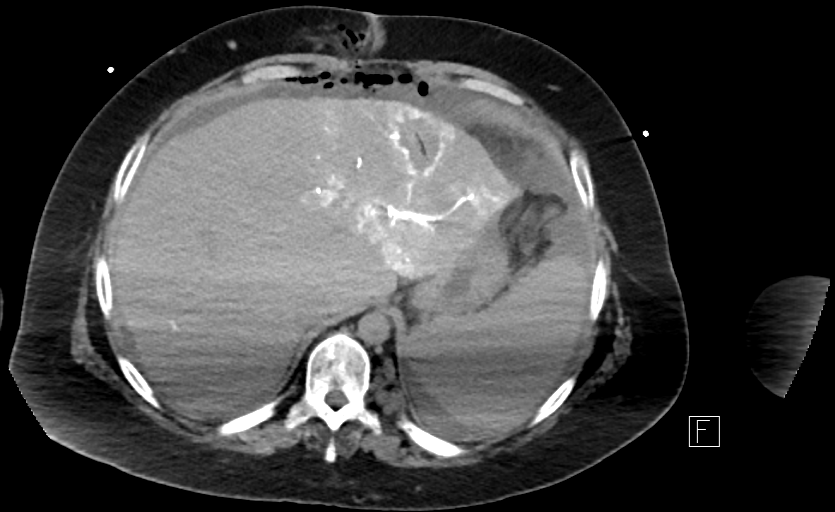

79 M with PMH of CKD, HLD, prostate cancer s/p prostatectomy + radiation presenting with feelings of fogginess, upset stomach, and diarrhea. Originally worked up at OSH, imaging concerning for a hepatic mass.

148/77 mmHg / 95 bpm / 15 breaths/min / 98.1°F / 98 ORA

sclera anicteric, no jaundice

AST 112, ALT 34, Alk Phos 202, CEA 2, CA 19-9 4